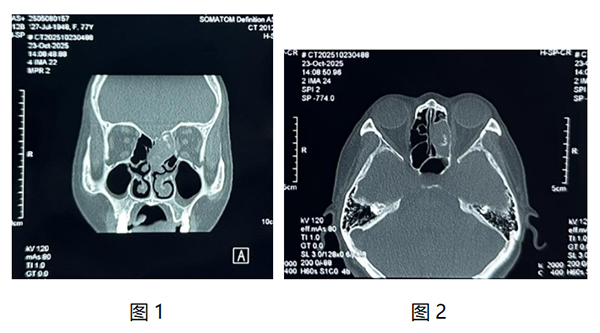

我院耳鼻咽喉頭頸外科近日為一名77歲老年患者實(shí)施鼻內(nèi)鏡下篩竇開(kāi)放+竇內(nèi)病變清除術(shù),患者因“左側(cè)頭痛多涕1月”到我院檢查,入院查體可見(jiàn)左側(cè)鼻腔中鼻甲水腫,上鼻道大量棕黃色干痂。鼻竇CT檢查可見(jiàn)左側(cè)篩竇內(nèi)軟組織影,內(nèi)部密度不均。(如圖1、2)